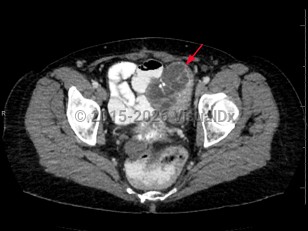

Ovarian cancer

In the United States, ovarian cancer is the deadliest gynecologic malignancy, resulting in more deaths than uterine and cervical cancers combined. It is the second most common gynecologic malignancy.

Patients with ovarian cancer are usually diagnosed with advanced disease, as the symptoms are often dismissed or overlooked by the patient and/or provider.